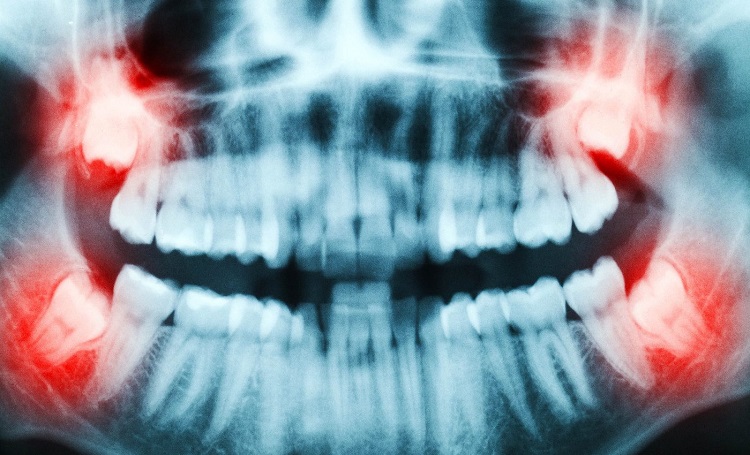

Os dentes do siso, muitas vezes vistos apenas como “incômodos” a serem extraídos, escondem um verdadeiro tesouro para a medicina: células-tronco capazes de tratar doenças graves. Pesquisas recentes mostram que a polpa dentária — tecido mole no interior do dente — abriga células capazes de se transformar em neurônios, músculos ou ossos, abrindo caminho para terapias regenerativas inovadoras.

Nos Estados Unidos, cerca de 10 milhões de dentes do siso são removidos anualmente, a maioria descartada. No entanto, cada dente recém-extraído oferece uma oportunidade de coleta indolor de células-tronco, que podem ser armazenadas em laboratórios especializados e utilizadas futuramente no tratamento personalizado de doenças como Parkinson, Alzheimer, insuficiência cardíaca e lesões articulares.